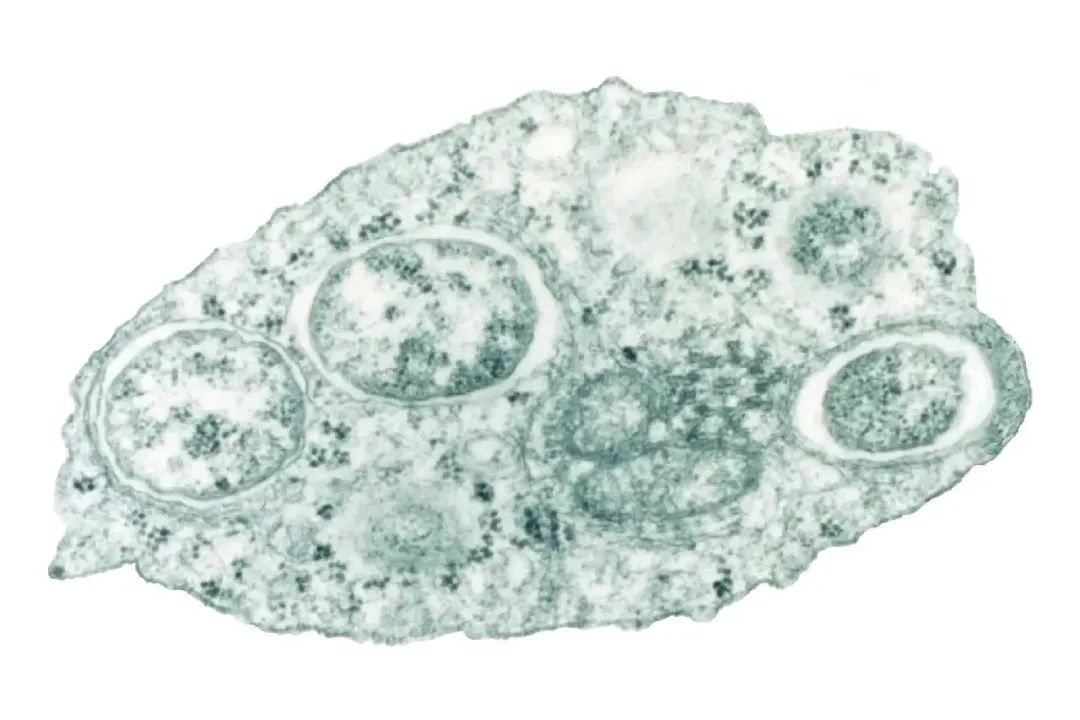

沃尔巴克氏菌|图片来源:Scientific American

首先,蚊子体内的沃尔巴克氏菌会和登革热病毒争夺资源,挤占了后者的生存空间。这也就是说,有了沃尔巴克氏菌,登革热病毒便不容易在蚊子体内复制,蚊子在叮咬人类的时候就更不容易传播登革热病毒。

其次,沃尔巴克氏菌还能让雄性蚊子“不育”。研究人员发现被该细菌感染的雄性蚊子,与未被感染的雌性蚊子交配后,它们的受精卵会因为细胞质不兼容而死亡,约等于变相让人家断子绝孙。